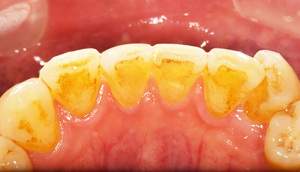

歯石除去

治療前

治療後

| 年齢 | 25歳・男性 |

| 主訴 | 歯石をとりたい・検診 |

| 治療内容 | 各種検査・歯石除去 |

| 治療期間 | 60分 |

| 費用 | 初診料3,000〜4,000円前後 +歯石除去約1,000円 |

| リスク・副作用 | ・処置後に歯がしみることがあります。 ・歯と歯の間に隙間ができるので、息が漏れ発音しにくいと感じることがあります。 ・歯ぐきの炎症が軽減すると歯ぐきが引き締まり、歯が長く見えることがあります。 |

| 担当者所見 | 前歯の裏側にすぐに歯石が溜まってしまいザラザラして気になるとご相談いただいたので適切な歯ブラシの当て方とフロスの通し方をお伝えさせて頂きました。 |